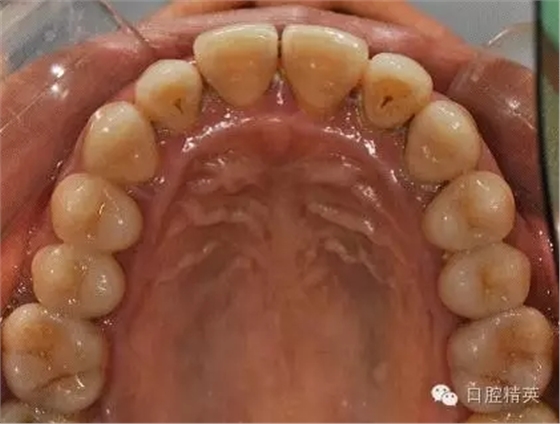

本病例 :女 34歲,主訴刷牙出血,覺(jué)牙齒輕度松動(dòng)一年。

檢查見(jiàn)大量齦上及齦下結(jié)石,探診出血,牙周袋較深,32-42 II度松動(dòng)。X線片顯示牙槽骨水平吸收。

診斷:成人慢性廣泛性中度牙周炎。

治療計(jì)劃:口腔衛(wèi)生宣教,刷牙指導(dǎo),齦上潔治,齦下刮治術(shù),下頜牙33-43牙周固定。

治療前: